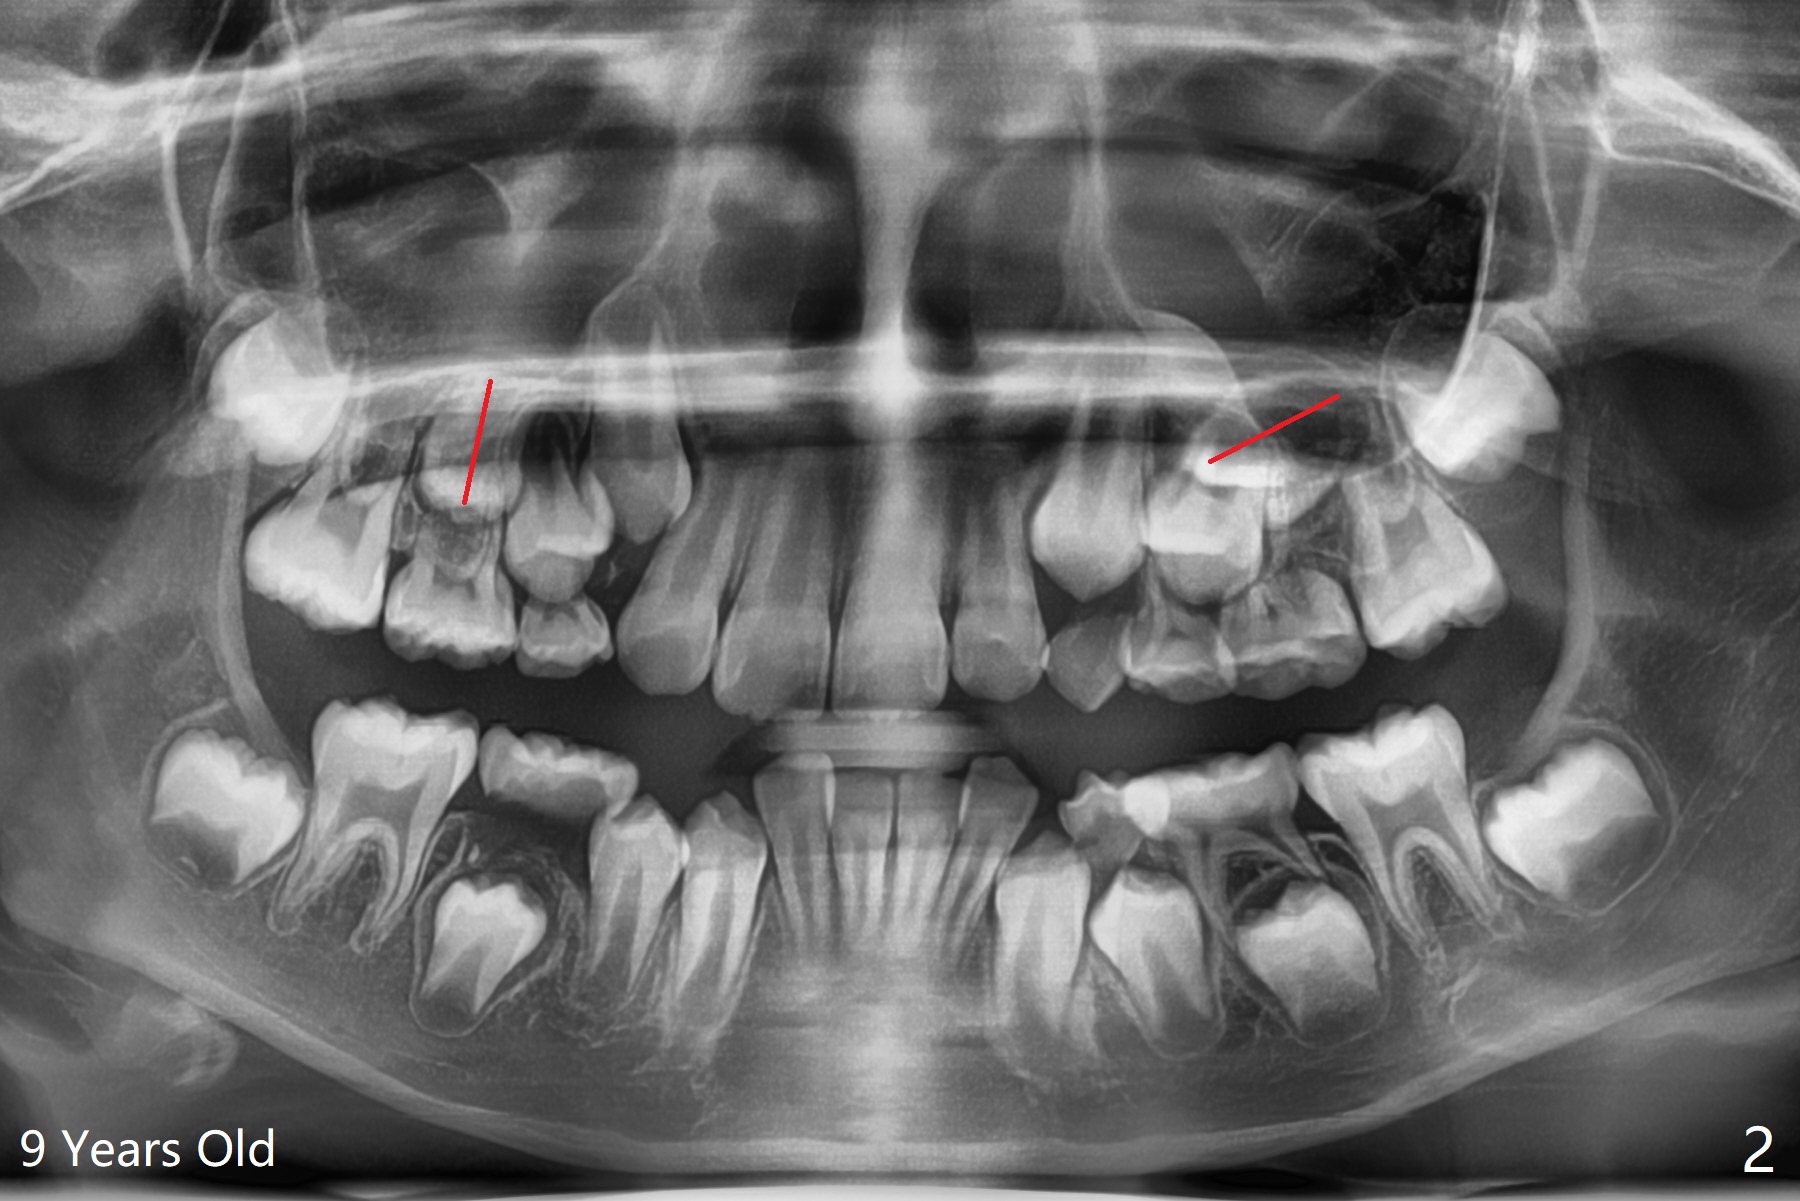

一位女孩具有家族性牙齿拥挤史,6岁下中切牙刚萌出时就显示拥挤(图一),九,十一岁相当明显(图二,三),十一岁正好处于新冠病毒流行期间,妈妈同意拔除四个第一双尖牙,让牙列自行调整一年左右。初步检查表明上下磨牙近远中位置正常。不紧不慢使用弓丝排列牙弓,让7充分萌出。牵引上尖牙时,注意磨牙位置改变,最好同时使用下6(二类牵引)以及上5-7作为支抗。